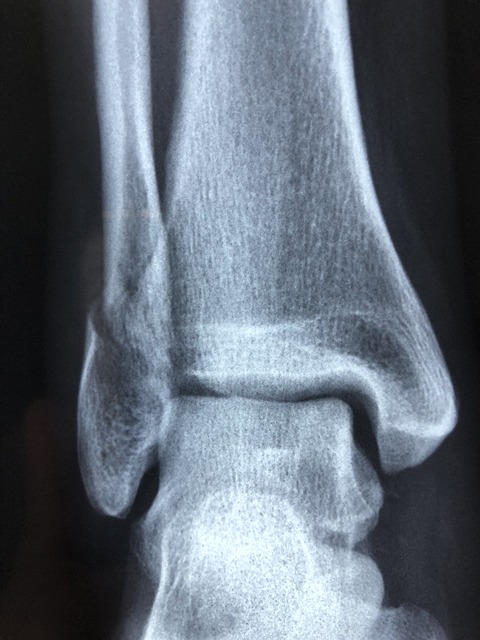

측 방향 검사

검사 목적

측면 상에서 먼 쪽 종아리뼈와 정강뼈, 발목관절, 목말뼈와 발꿈치뼈를 관찰할 수 있습니다.

영상의 평가

발목관절 중앙이 상 수용체 중앙에 나타나야 하며, 거퇴관절 윗부분 관절 사이가 균일하게 분리되어 나타나야 합니다.

바깥쪽 복사와 종아리뼈 먼쪽부분은 정강뼈 뒤쪽 1/2 또는 1/3, 목말뼈 뒤쪽 반과 겹쳐 나타나며, 목말뼈와 발꿈치뼈 전체가 보이고 인접한 발목뼈가 보여야 합니다.

적절한 노출로 종아리뼈 먼쪽부분의 윤곽과 연부조직이 선명하게 관찰되고, 모든 뼈의 미세구조와 면이 선명하게 보여야 합니다.